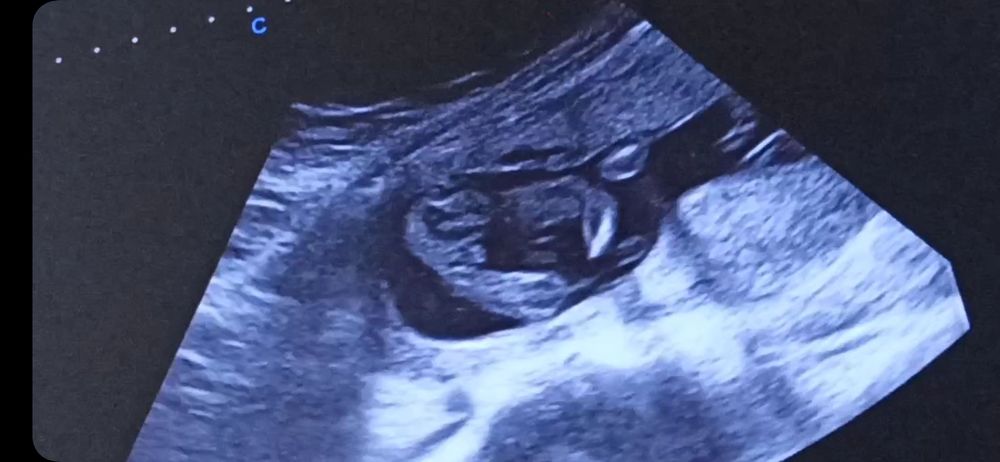

УЗИ в 17 неделек. Пол?

Пол малышаВопрос знатокам? Кто разбирается? Это мальчик или девочка?

Прикрепляю несколько противоречивых скринов с видео.

Врач очень не уверена предположила. Малыш крутился.

Как будто фотки разных детей) первая как девочка, а дальше уже больше на мальчика.

Антонина Соколова, по первым фото похожа на девочку .Но дальше есть что -то … пусть будет пуповина. Первое фото это скрин с видео ,я там прокручиваю и смотрела ,попробуйте и вы ,чтобы понять что там между ножек

Татьянка, я так и делала. Это всё скрины с одного минутного видео. Уже поставила на замедленное воспроизведение, смотрела изучала. Весь инет перерыла сравнивала. Ну чисто 50/50)))) кума говорит, на девочку похожа, я думаю что похоже на мальчика, муж бредит девочкой и говорит мне, что у мальчиков мошонка должна быть и где она, её нет. Врач предположила мальчика. Но не уверенно.